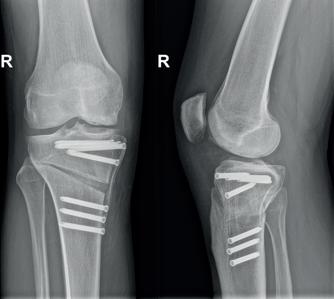

Met een zaag en beitels wordt het bot doorgenomen en gekanteld in de gewenste positie. Zoals eerder vermeldt kan dit enerzijds door een wig weg te nemen (closing wedge) of door de zaagsnede open te krikken (opening wedge). De correctie wordt peroperatief dmv fluoroscopie gecontroleerd en de osteotomie wordt gefixeerd dmv plaat en schroeven (foto 5)

Postoperatieve controles vinden meestal plaats na 2 weken (wondcontrole + radiografie), 6 weken (+ radiografie om callus progressie in te schatten) en 3 maanden (+ radiografie om consoli datie vast te stellen en ascorrectie te controleren) (foto 6).

Foto 5 Postoperatieve face en profiel radiografie. De osteotomie is gefixeerd dmv een carbonplaat die deels radiolucent is waardoor deze moeilijk zichtbaar is. Deze plaat heeft gunstige biomechanische eigenschappen (vergelijkbare elasticiteit) tov bot wat genezing ten goede komt. De schroeven zijn standaard roestvrij staal dus goed zichtbaar op radiografie.